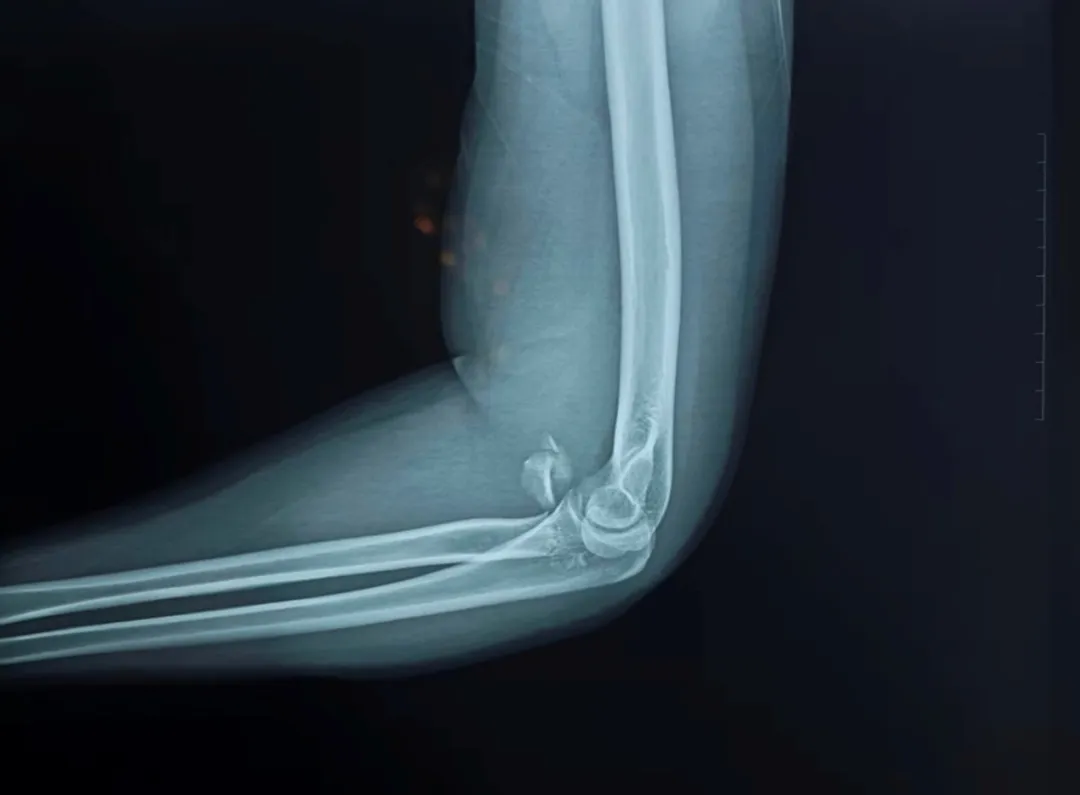

患者为朔州地区一名青壮年男性,因意外跌倒导致左肘"桡骨头粉碎型骨折"。经影像检查显示,其桡骨小头骨折粉碎严重,骨折块碎为三块较大骨块及多块细小碎块,且移位明显。面对这一复杂病例,骨关节科团队经过充分讨论,最终决定采用桡骨小头置换术。

手术由黄建军副主任医师主刀,带领团队成员路博丞博士、张学亮主治医师等共同完成。手术历时90分钟,成功植入人工桡骨头假体。术后一周复查显示,患者患肘旋前旋后功能完全恢复,屈伸功能达到健侧的80%。